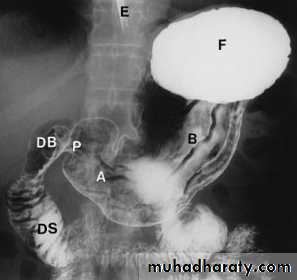

Barium meal examination (the patient instruct to fast at least 6 hours then drinks about 200 cc of barium) is now rarely performed.Upper GI endoscopy is widely used as the initial investigation in patients with possible disease of the stomach and duodenum. It enables the mucosa of the stomach and duodenum to be directly inspected and biopsied.

Gastric carcinoma

At barium examination, gastric cancer typically produce an irregular filling defectLinitis plastica is a severe diffused carcinoma resulting in narrowed rigid stomach.

Gastric outlet obstruction

Gastric outlet obstruction result in gastric dilatation .The causes are:

1. chronic duodenal ulceration

2. carcinoma of antrum3. duodenal, ampullary and pancreatic carcinoma

4. acute or chronic pancreatitis including pseudocyst formation

5. poor functional patency of a gastroeneterostomy

6. pyloric stenosis in infants (US shows a thickened, elongated pyloric canal)

Hiatus hernia

A hiatus hernia is a herniation of the stomach into the mediastinum through the esophageal hiatus in the diaphragm. Two main types: sliding and rollingSliding hiatus hernia: is the commoner type. The gastroesophageal junction and a portion of stomach are situated above the diaphragm. The cardiac sphincter is usually incompetent, so reflux from the stomach to the esophagus occurs readily and this may cause esophagitis, ulceration or peptic stricture

Rolling or para-esophageal hernia: the fundus of the stomach herniates through the diaphragm, but the gastroesophageal junction often remains competent below the diaphragm.